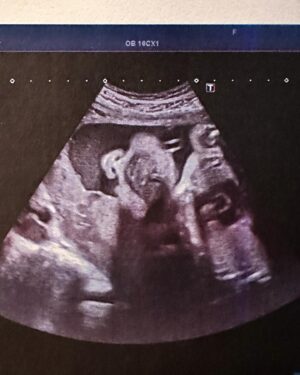

20.9K Likes – Sofia Arruda Instagram

Caption : As “fotografias” da nossa princesa 🥰 Não vemos a hora de te pegar ao colo, mas por enquanto ficas no forninho até à Primavera 🌸 #babygirl #pregnancyjourney #loveLikes : 20949

20.9K Likes – Sofia Arruda Instagram

Caption : As “fotografias” da nossa princesa 🥰 Não vemos a hora de te pegar ao colo, mas por enquanto ficas no forninho até à Primavera 🌸 #babygirl #pregnancyjourney #loveLikes : 20949